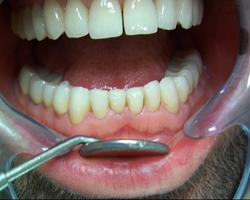

Les 14 couronnes supérieures céramo-céramiques sont collées.

Vue finale